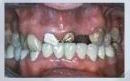

Восстановление отсутствующего зуба

не вредя соседним

Восстановление группы зубов - не вредя соседним и без нагрузки на соседние